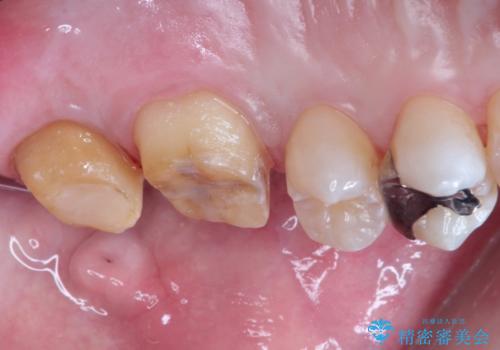

- 矯正の治療後に目立つ金歯を白くしたいとのことで治療することとなりました。

左上の奥歯に大きな金歯と、その後ろの歯が矯正治療用の仮歯が装着されていました。

これらの歯にオールセラミッククラウンを装着することとなりました。

総合治療が可能な当院ならば、矯正後のセラミックの装着がスムーズに行うことが可能です。